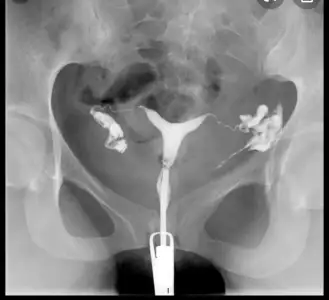

Filmden anlayan varsa bakabilir mi? Bi radyologa sorduk sol normal tüp görüntüsü o boğum boğum olan dedi, sağda da tıkanıklık varmış ama görünüyor opak madde geçmiş dedi. Bi sağlık çalışanına daha sorduk o da opak madde geçmiş yapışıklığı açmış dedi sizce? Turuncu olan az verdiği hali pembe olanlar basınçlı verdiği hali

Cnm ilk hali gibi degil tabi açılmış ama kısmen açılmış olabilir çünkü diğerinde bariz daha güzel geçiş var bu biraz daha az geçirmiş gibi geldi bana

Evet canım basınçlı verdikten sonra diğer tarafta saç kılı gibi bak işte o açılmış mı demek oluyor noluyor onu doktor söylicek

Baksana kuzum sende şöyle incecik geçiş yolu görünüyor mu? Varsa açılmıştır bence. Ben senin görselinde ikisinde de bu ince yolu göremedim ama geçtiğine göre olmasın lazım.